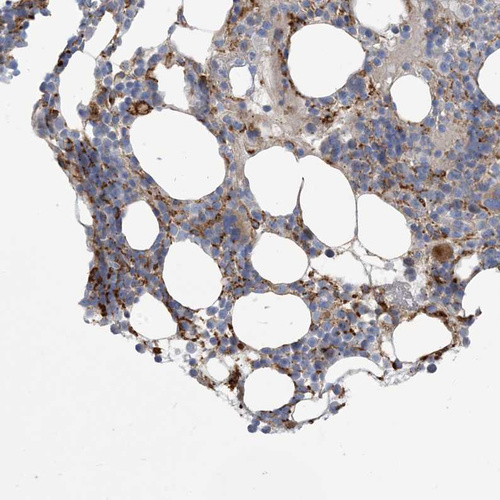

Immunohistochemical staining of human bone marrow shows moderate membranous positivity in hematopoietic cells.